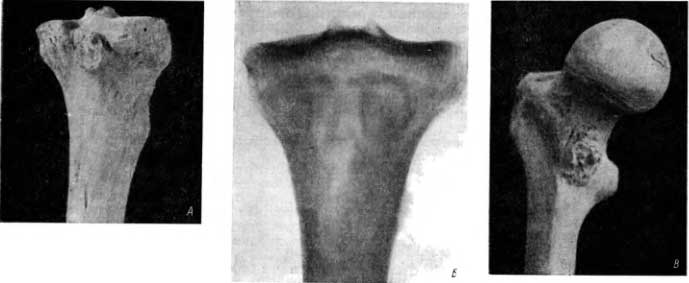

Заслуживает внимания следующая находка на кости из погребения в Саркеле. В правой большеберцовой кости крепкого мужчины (с хорошо развитым рельефом кости) была обнаружена остеохондрома, т. е. смешанная опухоль, состоящая частично из кости, частично из хряща. Хрящ в земле разрушился. Остеохондрома располагалась на задней поверхности кости, на границе метафиза с эпифизом, позади суставной впадины для малоберцовой кости (рис. 64, А).

Рис. 64. А — остеохондрома большеберцовой кости; Б — рентгенограмма большеберцовой кости с остеохондромой, видна кольцевидная тень, которую можно смешать с полостью; В — остеохондрома на бедренной кости.

В этой остеохондроме костного вещества было мало, превалировала хрящевая часть опухоли. В отличие от хрящевого экзостоза остеохондрома располагается в виде массивной нашлепки, уродливо утолщая кость. Основная масса опухоли вдавалась в прилегающие сзади этой кости мягкие ткани.

Между тем хрящевой экзостоз, имеющий только основание из кости, располагается под углом к длиннику кости (его конец направлен к середине кости, сравни с рис. 57, А, Б, В).

Данный костный препарат заслуживает особого внимания рентгенолога, ибо на рентгеновском снимке в задней проекции обнаруживается картина, которую можно ошибочно рассмотреть как полость, а именно — ограниченный остеомиелитический очаг — абсцесс Броди (рис. 64, Б).

Периферический костный участок остеохондромы симулирует стенку полости. Он выступает на снимке в виде кольца. Однако кнутри от кольца хорошо видна структура большеберцовой кости, нет деструкции кости.

Кроме описанного случая, мы наблюдали еще один раз остеохондрому на левом бедре взрослого человека (из погребения в Красноярском крае, в Хакасской АО, X–VIII вв. до н. э.; раскопки З. Б. Альтмана). Остеохондрома располагается на границе шейки и малого вертела (рис. 64, В).